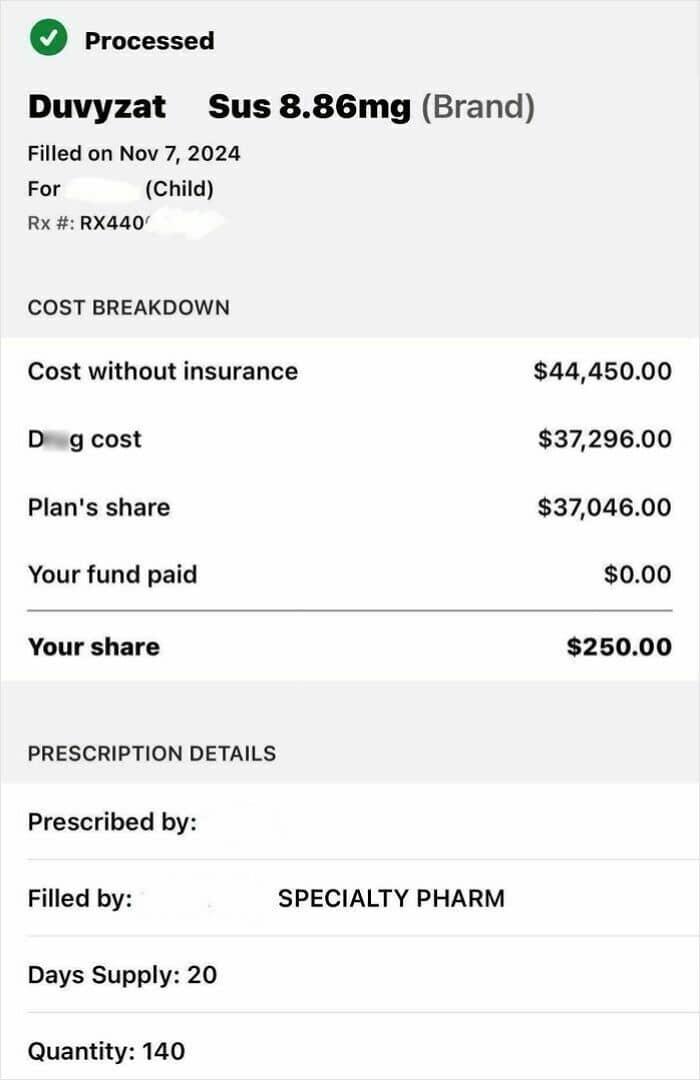

#74 My Sons New Prescription Medicine EOB

20 day supply and he won’t be stopping this medication, likely ever, if it works. Mind blowing.